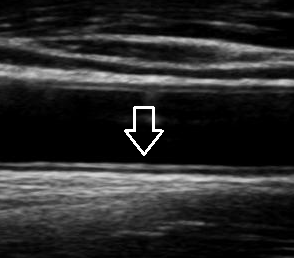

- 젤을 바른 후 초음파 탐촉자를 경동맥 위에 대고 영상 관찰

- 혈류 속도 측정과 플라크 유무 확인